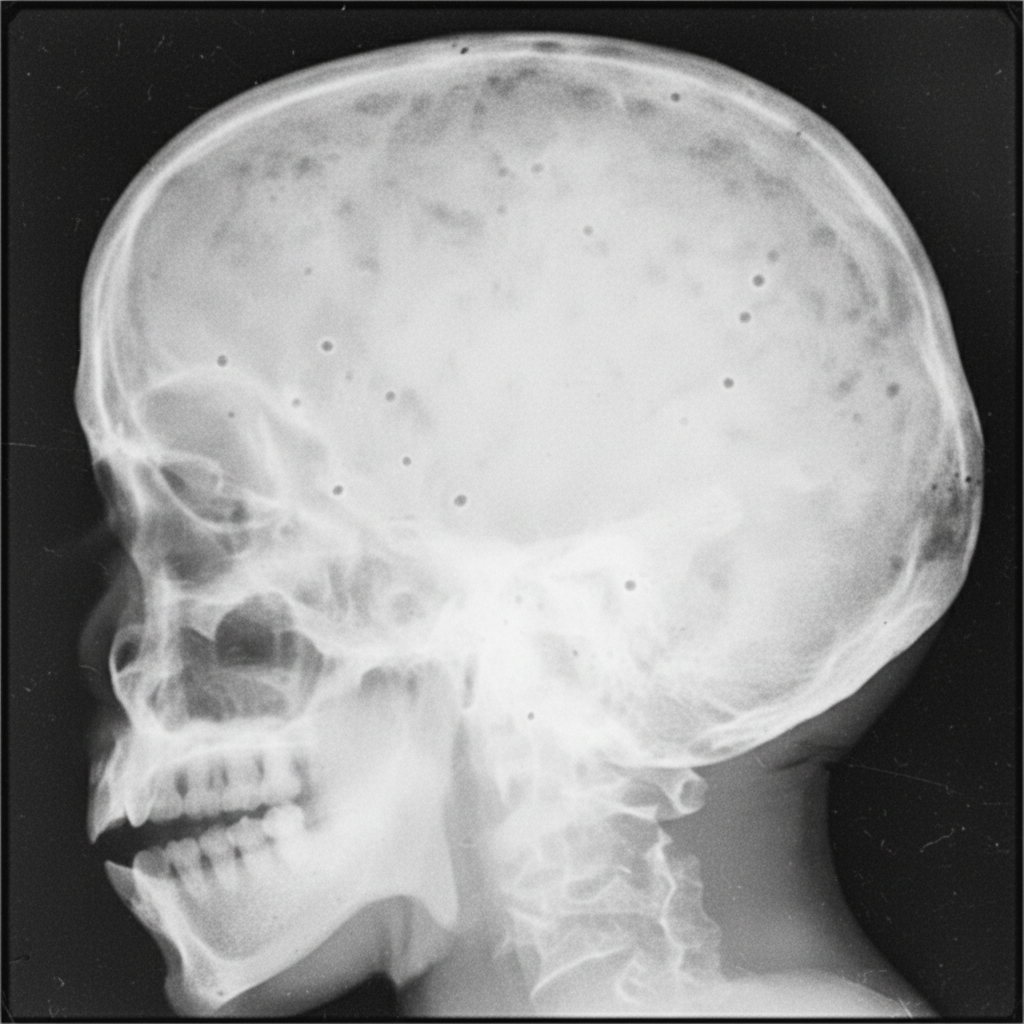

An X-ray of the skull shows multiple lesions. What is the most likely diagnosis?

Explanation: ***Multiple myeloma*** - Causes multiple **punched-out lytic lesions** on skull X-ray, creating the classic **"raindrop skull"** or **"pepper-pot skull"** appearance. - These lesions have **well-defined margins** without sclerotic borders and represent plasma cell infiltration causing bone destruction. *Paget's disease* - Skull shows mixed **lytic and sclerotic lesions** creating the **"cotton-wool"** appearance, not purely lytic lesions. - May also present with **osteoporosis circumscripta** (flame-shaped lytic areas) but typically has bone expansion and thickening. *Eosinophilic granuloma* - Usually presents as a **solitary lytic lesion** with **beveled edges** creating a "hole-within-hole" appearance on lateral view. - Part of **Langerhans cell histiocytosis** and rarely causes multiple skull lesions in adults. *Osteomyelitis* - Shows **ill-defined lytic lesions** with **irregular margins** and associated **periosteal reaction**. - Often accompanied by **soft tissue swelling** and **sequestrum formation**, which are absent in purely lytic lesions.